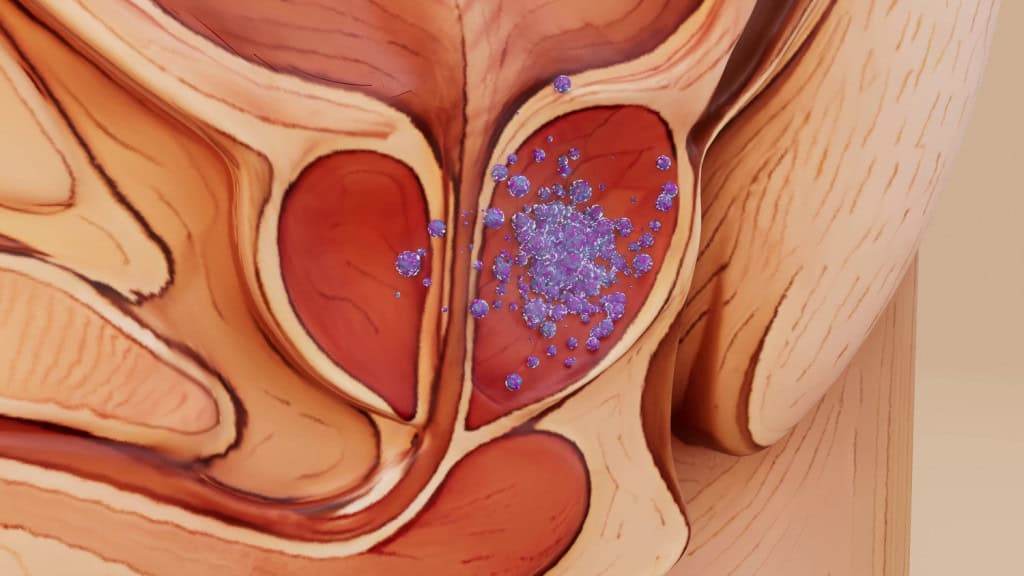

Médicos e pesquisadores que estavam na sessão plenária da American Society of Clinical Oncology (ASCO) se levantaram qua...

Ler maisResultados de pílula para câncer emocionam médicos em congresso de oncologia

Médicos e pesquisadores que estavam na sessão plenária da American Society of Clinical Oncology (ASCO) se levantaram qua...